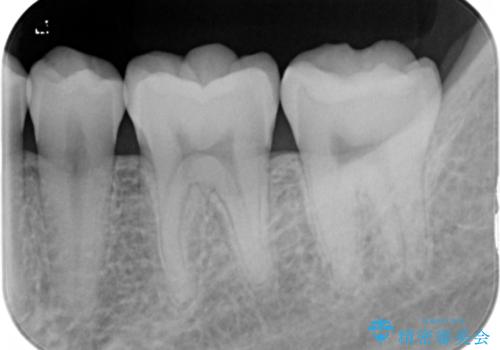

- 左下6、7番の虫歯をセラミックにて治療を希望された患者様です。

切削量を考慮してセラミックインレーを選択しました。

7番は虫歯が深かったのでCR裏層した上で形成、印象をしています。